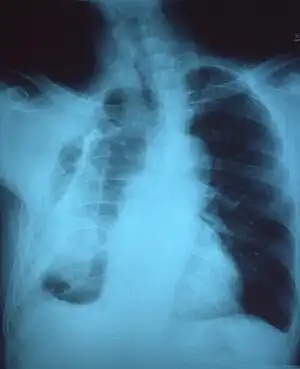

Extensive left-sided fibrothorax

Chest radiograph displaying inhomogeneous opacification of the left half of the chest that is fibrothorax